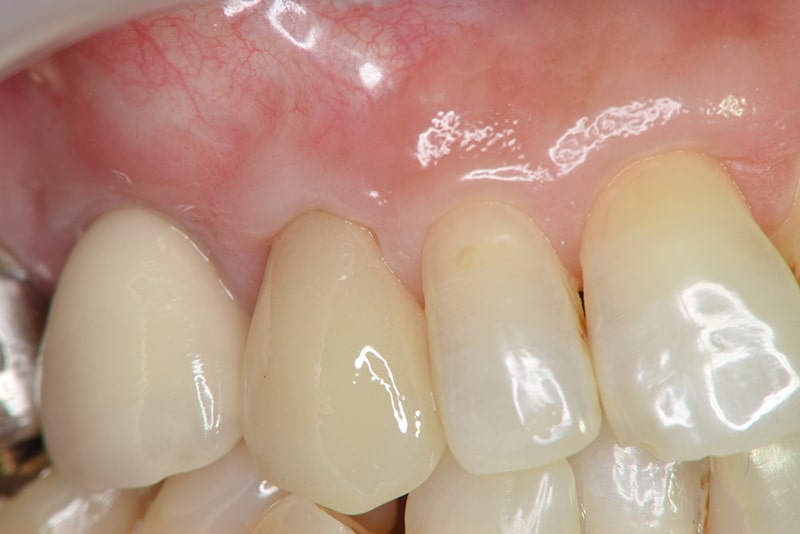

治療後

露出が目立たなくなり、歯肉のラインもきれいに改善された。